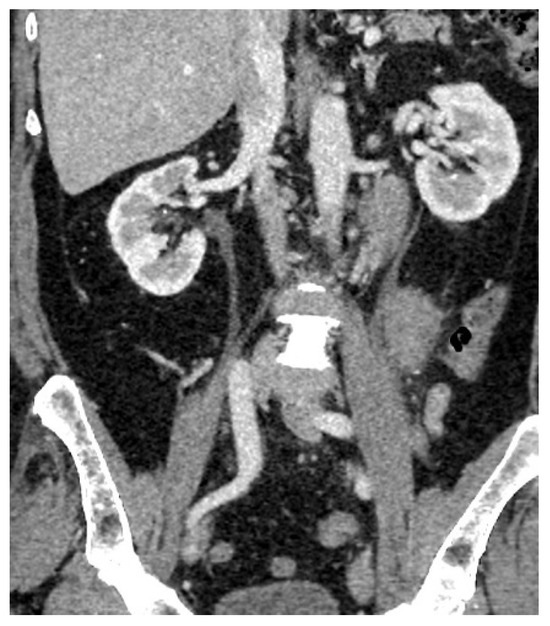

| 2 May 2023 | third emr: cardiac and colonic mass (+cns?) | nelarabine+cyclophosphamide+ etoposide |